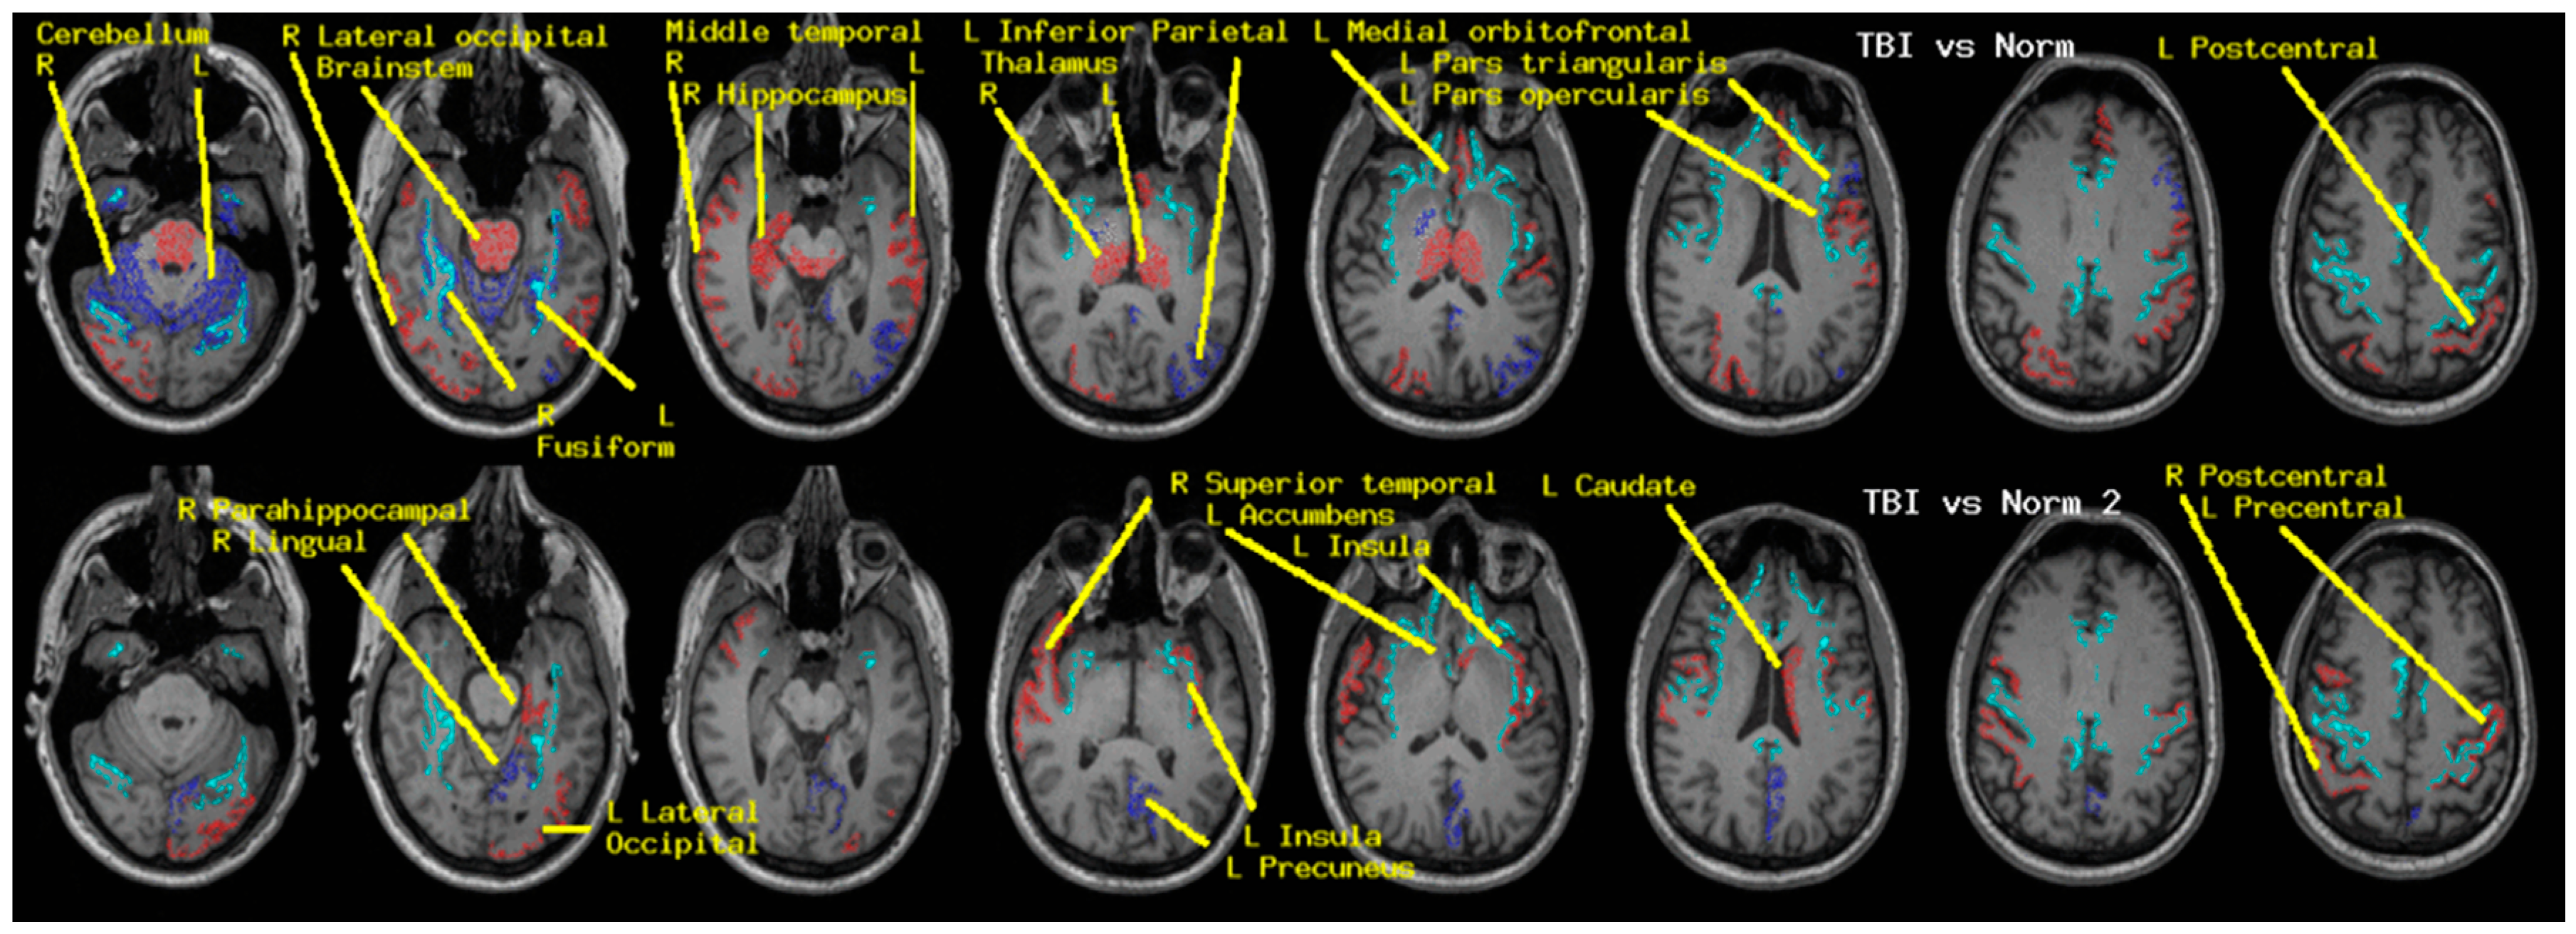

Regional measures of neuroelectric activity for 17 subcortical and 68 cortical regions were combined into classifiers using stepwise linear classification [16,17,18]. Classification accuracies with p-values are shown in Table 1 (Figure 1). The p-values were computed as follows. Considering line 1 of said table, 42 of 54 TEAM-TBI subjects who screened negative for insomnia were classified as negative and 12 as positive. The chance that this would happen by chance is equivalent to the odds of getting at least 42 heads when we flip a fair coin 54 times. For each symptom, both sides of the classification have significant p-values—i.e., the classifier does well in classifying both those who screen positive and those who screen negative. This provides confidence that the neuroelectric measures which comprise the classifier are related to the symptoms.

The regions whose measures were included are shown in Table 2 (Figure 1). For each symptom, a second classification function was constructed, for which the regions that were included in the first run were excluded. This second run produced significant classification accuracy for insomnia only, as indicated in the tables. This suggests (a) elevated confidence in the relationship between the regions whose neuroelectric measures were used for each classification and (b) that the regional measures included in the second classification function for insomnia are highly correlated with linear combinations of the first set. That is why they were not included in the first classification run.

Regional measures of neuroelectric activity for 17 subcortical and 68 cortical regions were combined into classifiers using stepwise linear classification [16]. Classification accuracies with p-values are shown in Table 5. The cortical and subcortical regions which contributed to the classifier in order of their statistical contribution were R thalamus, R cerebellum, R middletemporal, R hippocampus, R lateraloccipital, L isthmuscingulate, L thalamus, L fusiform, brain-stem, and 11 others. When these 20 regions were excluded, classification accuracy remained highly significant albeit reduced. The contributing regions in order were L insula, L lingual, R superior temporal, L caudate, L parahippocampal, and seven others.

6.1. Potential Clinical Utility

This study was undertaken to utilize and assess MEG-derived measures for the diagnosis and monitoring of treatment for chronic symptoms of TBI. We report results which demonstrate (a) sensitivity to the presence/absence of insomnia, somatization, depression, and anxiety (Table 1 and Table 3, Figure 1) and (b) sensitivity to history of concussion and/or chronic symptoms (Table 5, Figure 2, Figure 3, Figure 4 and Figure 5). We cannot directly tie these MEG results to TBI. However, for clinical purposes, the etiology may not matter so long as we can use the measures to more effectively diagnose and treat.